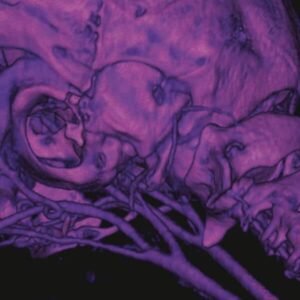

Preclinical Imaging Validation

Imaging studies demonstrate clear opacification of liver lobes and metastases in murine models following a single injection. Longitudinal monitoring confirms sustained enhancement suitable for quantitative assessment of lesion progression and therapeutic response.

Following administration, ExiTron™ nano 6000 accumulates in liver parenchyma, producing high contrast between healthy tissue and surrounding structures. This contrast facilitates clear identification of liver tumors and metastatic lesions, supports quantitative measurement of tumor burden, and enables monitoring of morphological changes over time. The low injection volume and favorable cardiovascular tolerability make the agent suitable for animals with limited physiological reserve.